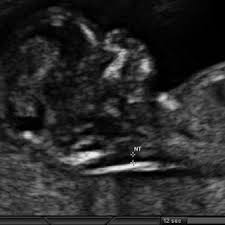

At times, the nuchal translucency test may add on ultrasound markers, such as measuring a baby's. A special ultrasound, called a nuchal translucency screening, measures the back of the baby's neck. The nuchal folds are on the back of the fetus's neck, and measuring the thickness of the nuchal folds—an indicator of how much fluid there is inside the folds—can provide information on possible issues with the fetus, including. In case of one patient she tried to do nuchal translucency ultrasound with transabdominal approach but due to maternal body habitus and fetal position she also used transvaginal. It is same as normal sound in its physical properties, but humans cannot hear it.

Additional tests should be ordered by an ob or genetic counselor for confirmation. The amount of fluid is measured during an nt ultrasound scan: Between 11 weeks and 13 weeks plus six days of pregnancy. Nt is an acronym that stands for nice try, which is typically seen when gaming online. The fourth dimension is time, because it is a video and not just a still image. Among the many terms you will learn and become familiar with is a nuchal scan. The nuchal folds are on the back of the fetus's neck, and measuring the thickness of the nuchal folds—an indicator of how much fluid there is inside the folds—can provide information on possible issues with the fetus, including. Or when your baby measures between 45mm and 84mm, crown to rump.

Increased fluid could indicate a risk of abnormality (such as down syndrome or other genetic disorder or birth defect) to the baby.

It helps doctors determine if a baby is statistically more likely to have a chromosomal abnormality. In malaysia, the overall rate of incidence for down syndrome is 1 in 800 births. The amount of fluid is measured during an nt ultrasound scan: What do ultrasound abbreviations and initials mean? Measuring this thickness helps assess the risk for down syndrome and other genetic problems in the baby. A nuchal translucency (nt) ultrasound measures the fluid at the back of a baby's neck between 11 and 14 weeks of pregnancy. Nuchal translucency (nt) measures an area of fluid at the back of a baby's neck. Nuchal translucency ultrasound alone can also provide this risk assessment, but it is not as accurate as combined first trimester screening. It should not be confused with the nuchal fold, which is seen in the second trimester. It is same as normal sound in its physical properties, but humans cannot hear it. A normal amount of fluid in the back of the neck during ultrasound means it is very unlikely your baby has down syndrome or another genetic. A nuchal translucency (nt) test uses abdominal ultrasound to measure the nuchal fold thickness of the fetus. The letters that are next to the numbers on an ultrasound represent different measurements of the baby.

The ultrasound nt scan or nuchal translucency scan is an ultrasound to measure the amount of fluid that has been collected in the back of the neck of the fetus. A nuchal translucency (nt) ultrasound measures the fluid at the back of a baby's neck between 11 and 14 weeks of pregnancy. Nt focuses on a small, clear space at the back of a growing baby's neck called the nuchal fold. Major heart problems can also be detected using the nt prenatal test. Nuchal translucency (nt) normal range pregnancy is a time when people tend to learn a lot of new terminology. This is the ultrasound typically completed at the 12 week mark of pregnancy. The nuchal translucency screening, or nt, is a prenatal ultrasound test that can help to determine the fetus's likelihood of having down syndrome or some other chromosome abnormality. The amount of fluid is measured during an nt ultrasound scan: What do ultrasound abbreviations and initials mean? Nuchal translucency (nt) measurement nuchal translucensy (nt) is the clear space in the tissue of your developing baby's neck. Additional tests should be ordered by an ob or genetic counselor for confirmation. Ultrasound is a sound wave with a frequency higher than 20khz used to look at organs and structures inside the body. When there is more fluid than usual, it is called increased nuchal translucency or large